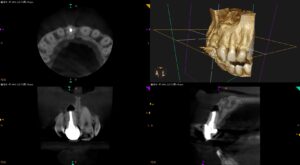

前歯の被せた歯が食事をすると痛い、硬いものが噛めない…〜Submarginal Flapによる #8 Apicoectomy

紹介患者さんの治療。 主訴は、 前歯の被せた歯が食事をすると痛い、硬いものが噛めない… であった。 初診時検査(2025.5.1) #8 Cold N/A, Perc.(+), Palp.(+), BT(-), Peri … 続きを読む 前歯の被せた歯が食事をすると痛い、硬いものが噛めない…〜Submarginal Flapによる #8 Apicoectomy